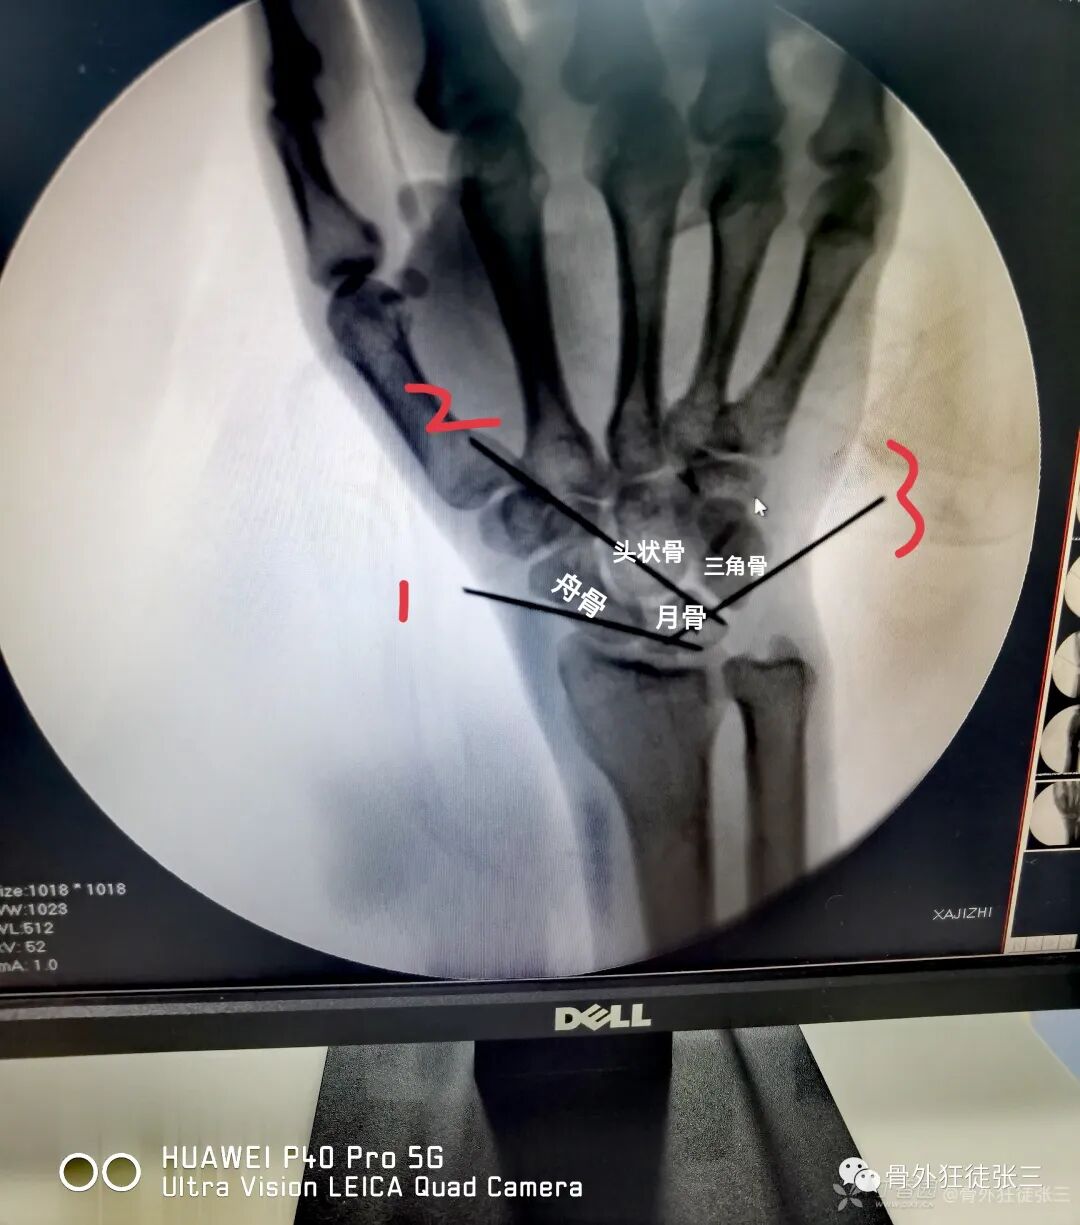

病例3,新鲜舟骨骨折,经皮Herbert钉

病例4,新鲜舟骨骨折,经皮Herbert钉

病例49,陈旧性月骨脱位,克氏针固定